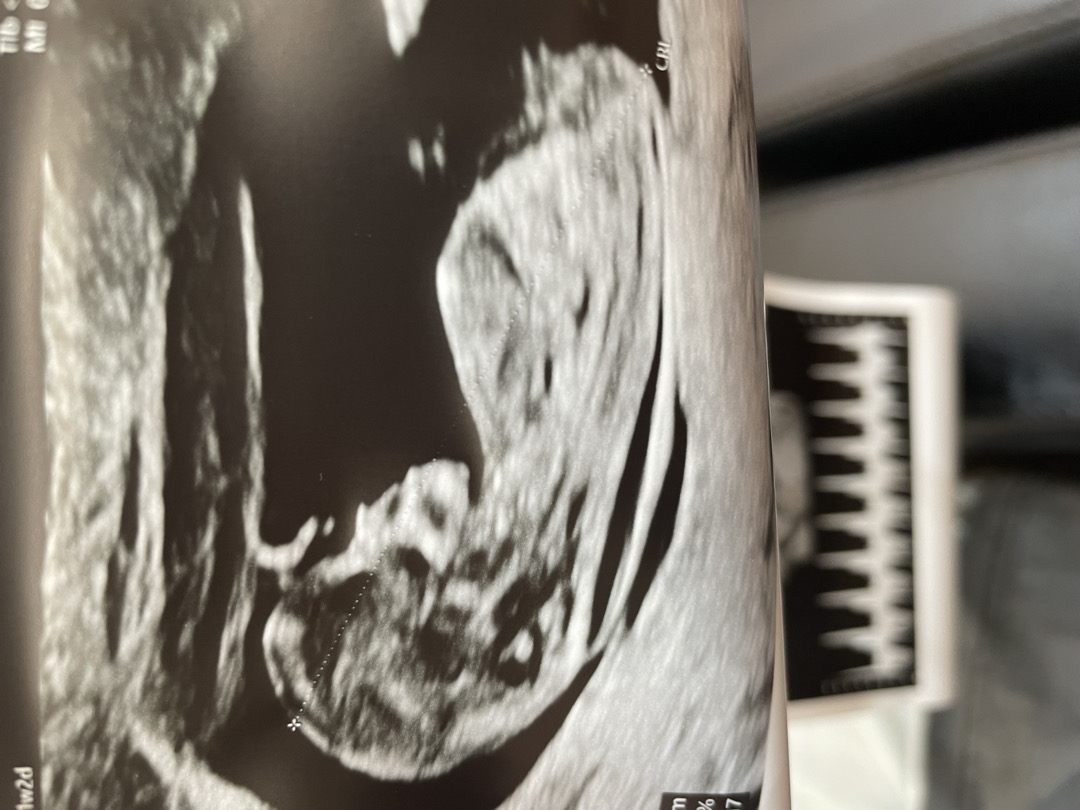

11주2일 각도법

11주 2일 초음파인데 각도법 봐주세요 ! ㅎㅎ 아들일까 딸일까 너무 궁금하네용🫣